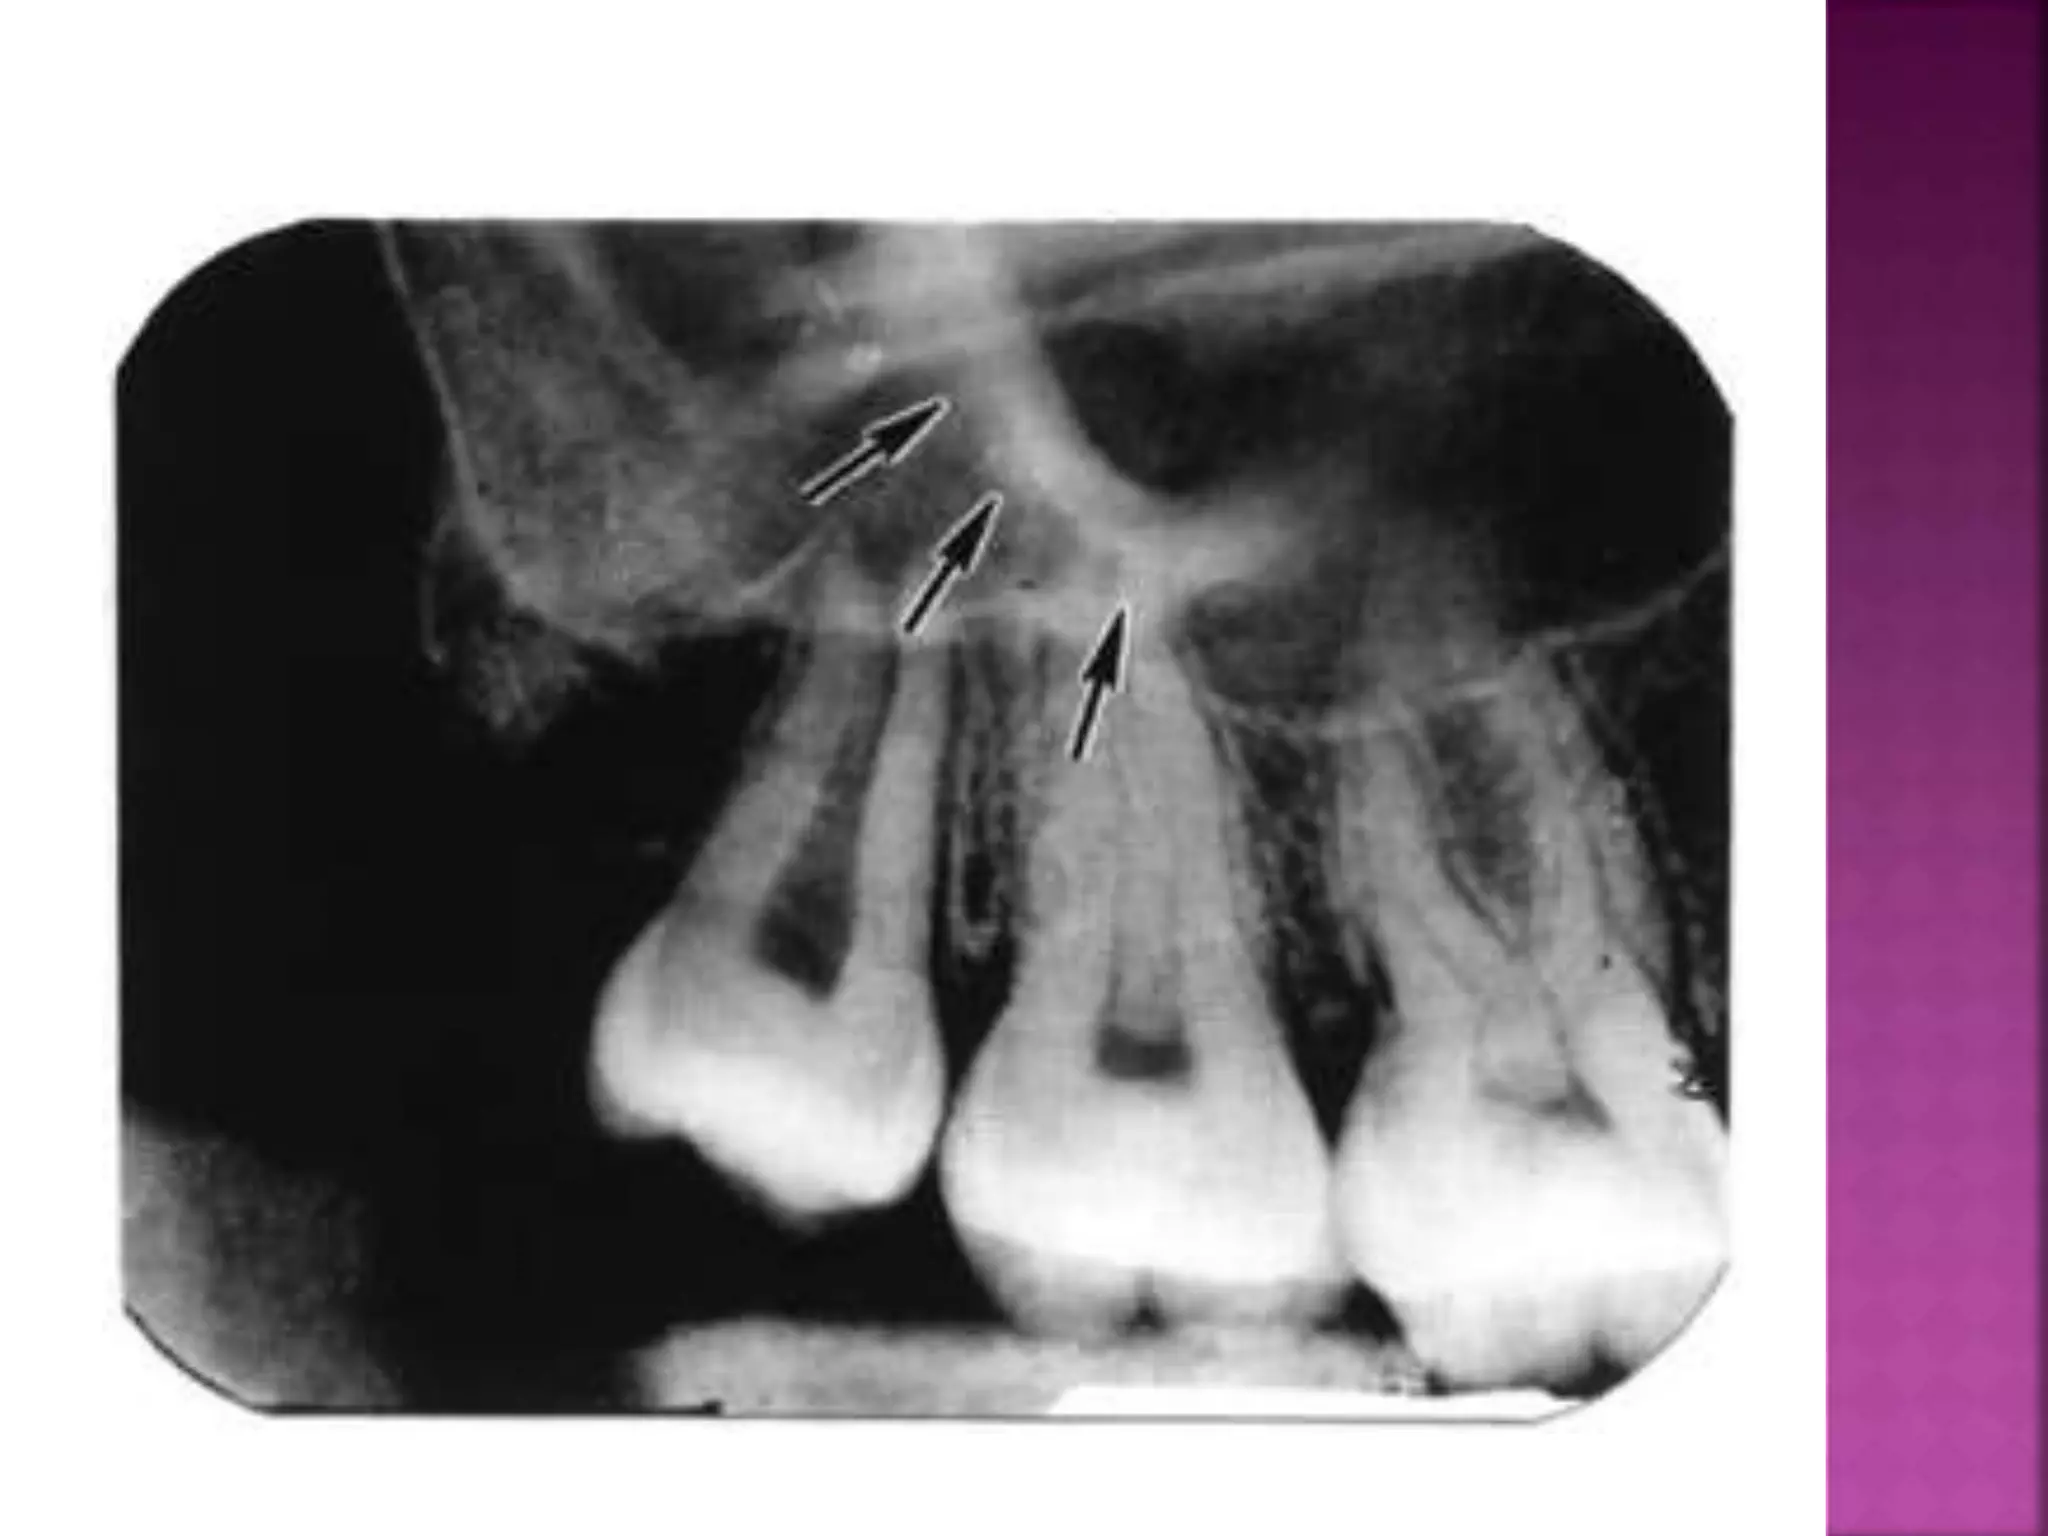

During mastication, certain stresses and strains are exerted not

only upon the alveolar bone but also upon the whole face and

anterior part of the base of the cranium. In order to withstand

these, the bones which are made up of thin plates are thickened

into well defined ridges. Most of these ridges pass upwards from

the alveolar bone towards the base of the cranium. Some, however,

lie transversely or antero-posteriorly to withstand forces in these

directions .

1 - The canine eminence which is a thickened ridge arises

from the region

of the upper canine . It extends upwarde on the facial

surface of the maxilla to the medial end of the infraorbital

margin and continues up the lateral wall of the nose to the

mesial end of the supraorbital ridge .

2 - The key ridge or the root of the Zygomatic process which arises

on the lateral wall of the maxilla over the roots of the first

permanent molars and becomes the zygomatic process . It

continues upwards to approximal contact .The anterior coinpenent

of force on one side of the arch cancels out that of the other side

in the midline provided that there is an intact dental arch. If the

interproximal contacts are destroyed by loss of teeth, those behind

the gap tend to drift forward, whilst those in front will lack

forward development